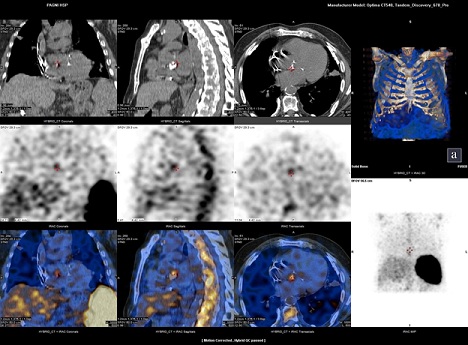

Due to his recent cardiac device implantation, a radiolabelled leucocyte scintigraphy was performed, which was positive for lead infection (Figure 2).

Figure 2: Radiolabelled Leucocyte Scintigraphy. 99mTc-HMPAO-WBC scintigraphy revealed the presence of CIED-associated infection.

Last but not least, according to ESC guidelines, clinical presentation of CDRIE is frequently ambiguous and echocardiography and blood cultures are the cornerstones of diagnosis. A normal TTE does not rule out CDRIE and high suspicion is needed in the presence of unexplained fever in a patient with a CIED, whereas additive tools may be needed, such as radiolabelled leucocyte scintigraphy and 18F-FDG PET/CT scanning [10].

1. To understand that normal echographic examination does not rule out CDRIE and additive tools may be needed (radiolabelled leucocyte scintigraphy, 18F-FDG PET/CT scanning).